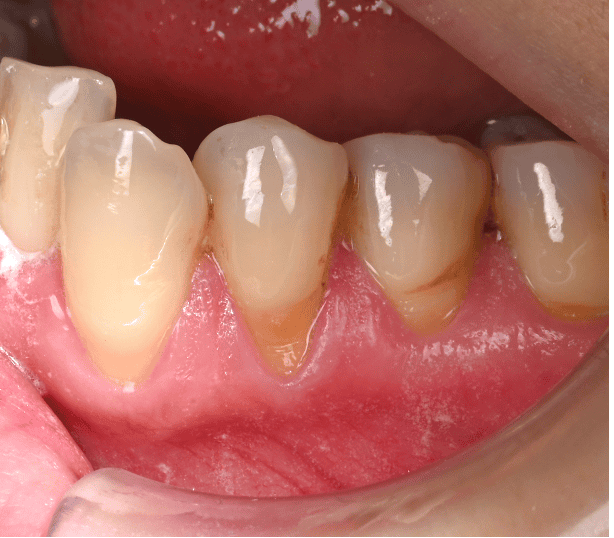

歯肉退縮治療例 治療例1: 40代 女性 ・歯茎が下がってきて、歯が染みてきた 治療前 治療後2年 治療期間 3ヶ月 治療費 5万/1本 (税別) 主な治療内容と概要 根面被覆術(結合組織移植術+歯肉弁歯冠側移動術) 左上の犬歯が伸びてきて染みるということで当院に来院されました。虫歯などはなく、歯茎が下がったことにより根の表面が露出し、知覚過敏の症状がでていました。知覚過敏の改善にはいくつかの方法がありますが、今回は見た目の改善などの患者さんの希望のため、歯肉を移植し、根を覆う処置を行いました。術後から染みの症状はなくなり、歯茎の位置も改善して満足されております。 考えられるリスク・副作用・注意点等 術後の歯肉退縮の再発予防のために決められた指導を守り、継続的なメインテナンスが必要 術後の痛みや腫れなどの症状がでることがあります。(基本的には鎮痛剤の服用などでおさまります) 治療例2: 60代 女性 ・歯ブラシをすると歯茎が痛くて出血する 治療前 犬歯の歯茎だけが大きく下がってしまい、歯の表面が虫歯になりかけている。 治療後1年 歯肉の位置は隣の歯と同様の高さに落ち着き、歯ブラシがしやすい形態に変化した。 治療期間 3ヶ月 治療費 8万/1本 主な治療内容と概要 根面被覆術(歯肉弁側方移動術+結合組織移植術+遊離歯肉移植術) 前歯の一本だけ歯茎が下がってしまい、歯ブラシがしにくい状態になっておりました。そのため、歯茎の炎症と根が一部虫歯に也変えており、今後更に歯茎が下がっていくことが予想されました。組織を移植し、根を覆う処置を行いました。また、硬い歯肉(角化歯肉)が少ないばあい、再発リスクが高くなるため、2回目の手術で硬い歯肉を移植することで、予後が良い状態に改善いたしました。歯肉のラインが横の歯とそろったことで歯ブラシがしやすくなり、現在も良い状態で維持されています。 考えられるリスク・副作用・注意点等 術後の歯肉退縮の再発予防のために決められた指導を守り、継続的なメインテナンスが必要 術後の痛みや腫れなどの症状がでることがあります。(基本的には鎮痛剤の服用などでおさまります) 治療例3: 30代 女性 ・これ以上歯茎が下がるのが不安 治療前 複数の歯の歯茎が下がってしまい、見た目や歯ブラシに影響がでている 治療後5年 歯茎の下がりが改善し、長期的に安定している。 治療期間 3ヶ月 治療費 13万/3本 (止血材込み) 主な治療内容と概要 根面被覆術(トンネリング法+結合組織移植術) 全体的に歯ブラシがお上手でしたが、年齢にしては歯茎が下がってしまい、見た目やブラシング時に不安を感じて来院されました。患者様は今後さらに下がることを恐れており、今回の手術を希望されました。複数歯の歯肉退縮のため、トンネリング法という方法で歯肉の下がりを改善しました。治療後5年たった現在も問題なく不安が解消されたと喜んでおられます。 考えられるリスク・副作用・注意点等 術後の歯肉退縮の再発予防のために決められた指導を守り、継続的なメインテナンスが必要 術後の痛みや腫れなどの症状がでることがあります。(基本的には鎮痛剤の服用などでおさまります) 当院では、歯周病専門医による歯肉退縮(歯茎の下がり)を回復する治療を行っております。 歯茎の位置を元に戻すことで、様々な不具合を改善することができます。また、歯肉を移植する方法を多くとりますが、歯肉を移植することで歯肉の厚みが保たれ、将来的に歯茎が下がることを予防することができます。 矯正治療などにより歯茎が下がった、また歯茎がすでに下がっており、矯正治療できないと言われたなど矯正治療に伴う歯肉退縮改善治療も多く行っています。ご紹介していただく場合は、担当の先生と矯正の開始時期等についてもご相談し、最適な時期に行うことができます。 もしご質問や治療ご希望の患者様はご予約の際に受付にお申し付けください。 歯科鈴木医院 (板橋区桜川 東武鉄道東上本線上板橋から徒歩7分) 2020.12.18 実際の治療例 治療例 本ページでは、当院での実際の治療例を示しております。 各治療例で紹介している治療による結果は個人差があり、治療効果を保証するものではありません。また、起こりうるリスクや副作用等を十分に理解し、担当医と相談して選択し… 2023.05.11 歯周病治療 治療例 歯周病治療例 治療例1: 40代 男性 ・歯医者が怖くてずっと行けていなかった。 ・歯が揺れてきて噛めない ・血が出るので歯ブラシが怖くてできない 治療前 … 2018.06.10 歯周病治療 トップページ 〉診療案内〉歯周病治療 歯周病認定医・専門医とは 歯周組織再生療法 歯周病とは? あなたは以下の項目のどれか当てはまることがありますか? ・朝起きたとき、口の中がネバネバする。 ・ブラッシング時に出…